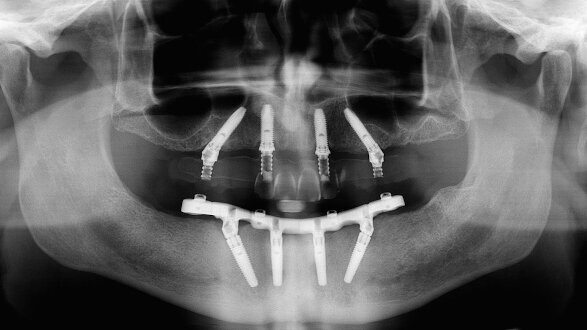

Objective: All-on-4 treatment concept is widely applied for complete-arch rehabilitations. Nevertheless, minor technical and biological complications can occur. The objective of this study was to evaluate the three-year clinical and radiographic data of complete-arch fixed dental prostheses supported by four implants according to the All-on-4 protocol.

Materials and methods: Thirty consecutive edentulous patients or patients with terminal dentition (18 females and 12 males; mean age of 67.4 years), with a preference for implant-supported complete-arch screw-retained fixed dental prostheses, were enrolled and treated according to the All-on-4 protocol between January 2008 and December 2011. The outcomes evaluated were implant and prosthesis survival and success rates, any technical and biological complications, periimplant marginal bone loss and patient satisfaction.

Results: One hundred and twenty regular platform implants were placed. No patients dropped out. One implant failed two months after placement, resulting in a cumulative implant survival rate of 99.2%. No definitive prostheses failed. Eight technical and three biological complications were reported in 11 patients during the entire follow-up period. At the three-year examination, the mean marginal bone loss was 1.52 ± 0.41 mm.

Conclusion: Within the limitations of the present study, the All-on-4 protocol was deemed a viable treatment concept for the complete-arch rehabilitation of both jaws in the medium term. Further long-term prospective studies are needed to confirm these results.